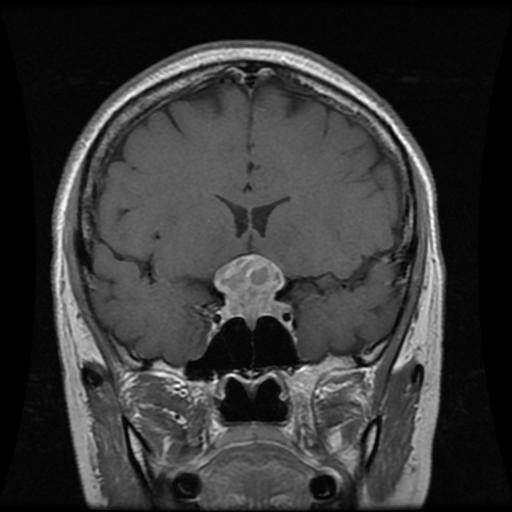

NeuroScan.AI is an advanced brain tumor classification system that: Analyzes MRI scans using deep learning Classifies different types of brain tumors with 92% accuracy Generates comprehensive medical reports Provides personalized treatment recommendations using Google's Gemini AI Creates detailed PDF reports with patient information, analysis results, and treatment plans Includes a section for doctor's review and approval

We built NeuroScan.AI using a sophisticated tech stack: Deep Learning: TensorFlow 2.15.0 with MobileNetV2 architecture Web Interface: Streamlit 1.32.0 for the user-friendly web application Image Processing: OpenCV 4.9.0.80 and Pillow 10.2.0 AI Integration: Google's Gemini AI for treatment recommendations Report Generation: FPDF2 for creating professional medical reports Data Processing: NumPy 1.24.3 and scikit-learn 1.4.1 The system was trained on a comprehensive dataset of brain MRI scans, fine-tuning the MobileNetV2 model to achieve optimal performance.